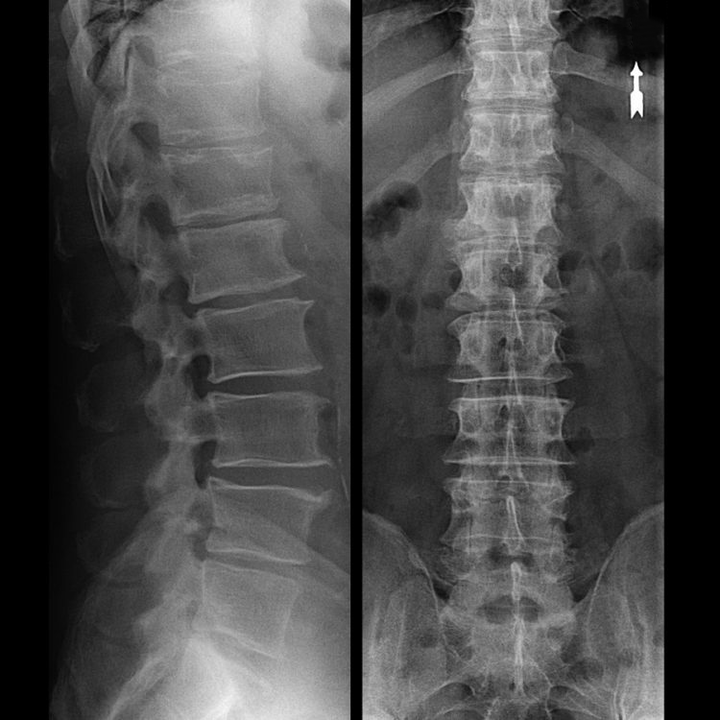

In typical cases, osteochondrosis of the cervical and cervical thoracic spine occurs, as described above.Therefore, the main phase of diagnosis was and remains to identify the patient's complaints and determine the presence of accompanying muscle spasms by simply palpating the muscles along the spine.Is it possible to confirm the diagnosis of osteochondrosis by X-ray examination?

An “X-ray” of the cervical spine and even functional tests for flexion and extension do not show cartilage because its tissue allows X-rays to pass through.Nevertheless, based on the location of the vertebrae, one can draw general conclusions about the height of the intervertebral discs, the general straightening of the physiological curvature of the neck - lordosis - as well as the presence of marginal growths on the vertebrae with prolonged irritation of their surfaces by brittle and dehydrated intervertebral discs.Functional tests can confirm the diagnosis of cervical spine instability.

Since the intervertebral discs themselves are only visible using CT or MRI, magnetic resonance imaging and X-ray computed tomography are indicated to clarify the internal structure of cartilage and formations such as bulges and hernias.Thus, with the help of these methods, an accurate diagnosis is made, and the tomography result is an indication and even an actual guide for the surgical treatment of an inguinal hernia in the neurosurgical department.

- You can regularly take at least one x-ray of the lumbar spine in two projections or an MRI to determine whether the hernia, if any, is progressing;